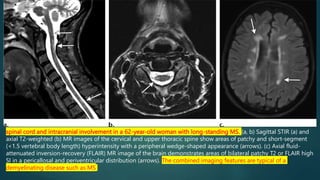

spinal cord and intracranial involvement in a 62-year-old woman with long-standing MS. (a, b) Sagittal STIR (a) and

axial T2-weighted (b) MR images of the cervical and upper thoracic spine show areas of patchy and short-segment

(<1.5 vertebral body length) hyperintensity with a peripheral wedge-shaped appearance (arrows). (c) Axial fluid-

attenuated inversion-recovery (FLAIR) MR image of the brain demonstrates areas of bilateral patchy T2 or FLAIR high

SI in a pericallosal and periventricular distribution (arrows). The combined imaging features are typical of a

demyelinating disease such as MS